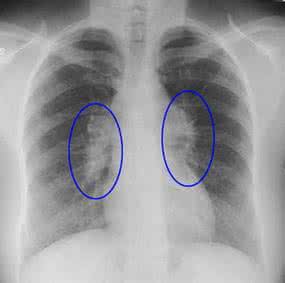

肺结节病(sarcoidosis)是一种病因未明的多系统多器官的肉芽肿性疾病,近来已引起国内广泛注意。常侵犯肺、双侧肺门淋巴结、眼、皮肤等器官。其胸部受侵率高达80%~90%。本病呈世界分布,欧、美国家发病率较高,东方民族少见。多见于20~40岁,女略多于男。目前我国(1987)年已报道560余例。

你好;肺结节为一种可侵犯全身多系统的慢性疾病,90%累及肺,其基本病变为形成非干酪样坏死性肉芽种。该病多见于中、青年女性,以肺、肺门淋巴结最常受累,也可累及浅表淋巴结、皮肤、眼、扁桃体、肝、脾、骨髓等处。最好进一步做肺穿刺活检做病理检查以明确诊断后治疗,密切观察祝您健康。